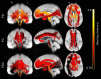

Aging is associated with widespread alterations in cerebral white matter (WM). Most prior studies of age differences in WM have used diffusion tensor imaging (DTI), but typical DTI metrics (e.g., fractional anisotropy; FA) can reflect multiple neurobiological features, making interpretation challenging. Here, we used fixel-based analysis (FBA) to investigate age-related WM differences observed using DTI in a sample of 45 older and 25 younger healthy adults. Age-related FA differences were widespread but were strongly associated with differences in multi-fiber complexity (CX), suggesting that they reflected differences in crossing fibers in addition to structural differences in individual fiber segments. FBA also revealed a frontolimbic locus of age-related effects and provided insights into distinct microstructural changes underlying them. Specifically, age differences in fiber density were prominent in fornix, bilateral anterior internal capsule, forceps minor, body of the corpus callosum, and corticospinal tract, while age differences in fiber cross section were largest in cingulum bundle and forceps minor. These results provide novel insights into specific structural differences underlying major WM differences associated with aging.